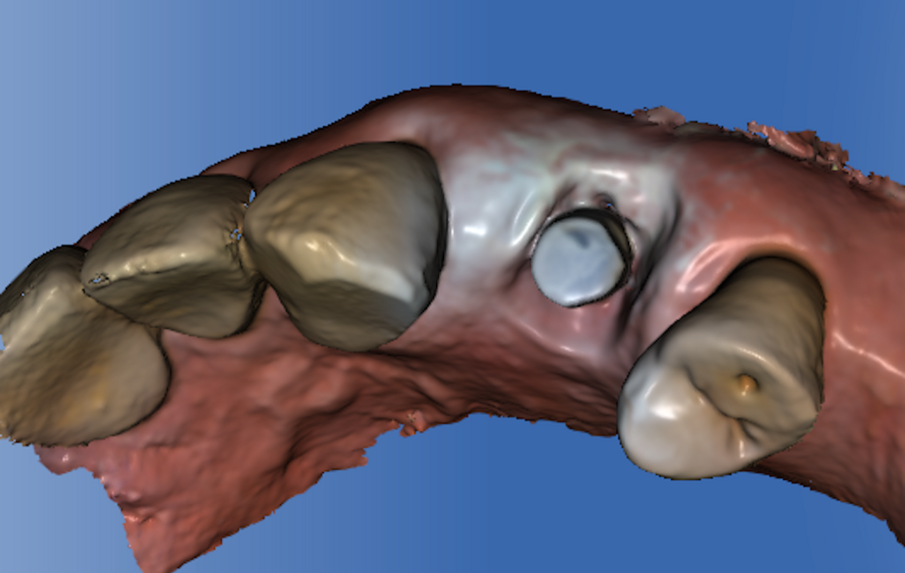

Per ridurre la perdita volumetrica dei tessuti perimplantari, alcuni studi clinici5-7 hanno riportato l’utilizzo delle cappette di guarigione customizzate avvitate sugli impianti immediatamente inseriti negli alveoli post-estrattivi. In questo case report viene descritta l’applicazione delle cappette di guarigione customizzate seguendo la procedure Cad-Cam in un flusso di lavoro digitale. Prima di eseguire l’estrazione si procede con il rilevamento dell’impronta digitale per copiare l’anatomia del profilo d’emergenza del dente. A questo punto si estrae in modo molto conservativo il dente. Si posiziona l’impianto dentale senza inserimento dei biomateriali nel void creato fra la superficie dell’impianto e la parete dell’alveolo. Si avvita una cappetta eseguita con la procedura Cad-Cam copiando l’anatomia del dente estratto (Figg. 1a, 2).

Fig. 2 - Coppetta di guarigione castomizzata avvitata sull’impianto appena inserito nell’alveolo post-estrattivo.